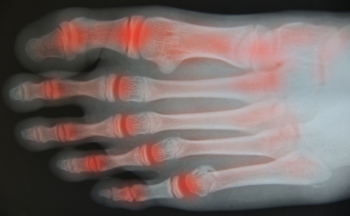

Gout is known to be a painful and uncomfortable condition that typically affects the big toe. This part of the foot may be so sensitive that the weight of a bed sheet may cause intense pain. There are additional symptoms that may be associated with gout, including redness, swelling and extreme heat that may radiate from it. This ailment is said to be caused by excess uric acid in the blood levels that originate from ingesting foods that are laden with purines. Many patients notice these severe symptoms in the big toe, although it may occur in other parts of the body. Specific medications may be prescribed once an attack of gout has occurred, and there may be preventative measures that can be implemented which can possibly avoid this painful condition from occurring. If you feel you may have gout, it is advised to speak with a podiatrist as quickly as possible to learn more about this condition, in addition to beginning the correct treatment.

Gout is a painful condition that can be treated. If you are seeking treatment, contact Brent Harwood, DPM from Southeast Podiatry. Our doctor will treat your foot care needs.

What Is Gout?

Gout is a form of arthritis that is characterized by sudden, severe attacks of pain, redness, and tenderness in the joints. The condition usually affects the joint at the base of the big toe. A gout attack can occur at any random time, such as the middle of the night while you are asleep.